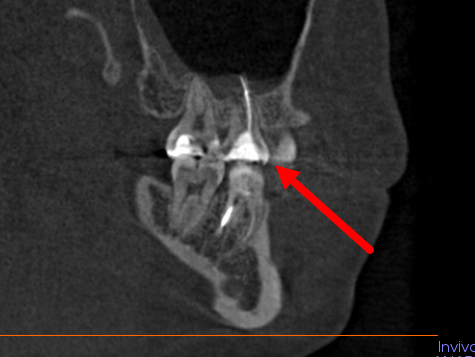

Врач второй клинике увидела на снимке 4 канала, и сказала, что первым врачом, лечившим зуб, были вылечены только 2. Также что вверху зуба инородное тело, его необходимо вытаскивать, лечение будет проходить в 2 приема. Нужно ходить с лекарством в зубе месяц и пытаться извлечь лишний материал от первого лечения через зуб, а в случае если не получится его оттуда вынуть через зуб, то пропихнуть его в пазуху и оно должно само через пазуху. Корни зуба находятся в этой пазухе.

Обратились еще в одну клинику, там врач сказал, что материал заложен неправильно, с пробелами, и выходит за пределы корня зуба. Зубных каналов пролечено 2, причем 3 она видит, а 4й нет. Также есть 2 варианта лечения: попробовать достать этот материал через зуб и проходить с лекарством 2 недели-месяц.

Либо если не получится достать материал на первом приеме, выход только пломбировать полностью зуб как есть и оставлять этот материал, и уже прорезать десну снаружи и доставать через десну.

Ниже прикреплю скриншоты 3Д снимка с проблемным зубом, если кому-то потребуется полностью 3Д снимок напишите почту или другие контакты, я пришлю полную версию снимка.